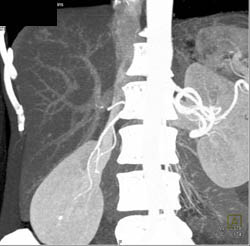

Focal Nodular Hyperplasia (FNH)